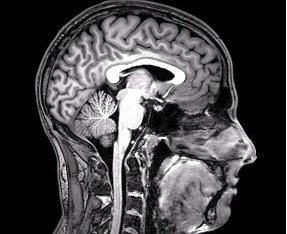

De onderzoekers maken gebruik van non-invasieve fMRI beeldvorming om de betrokken hersengebieden te identificeren en te onderzoeken hoe emotieregulatie de hersenplasticiteit op de lange termijn beïnvloedt. Daarnaast wordt gekeken naar hoe individuele verschillen, zoals genetische aanleg, van invloed kunnen zijn op het vermogen tot emotieregulatie. Dit aspect zou kunnen verklaren waarom sommige mensen beter in staat zijn hun emoties te beheersen dan anderen.